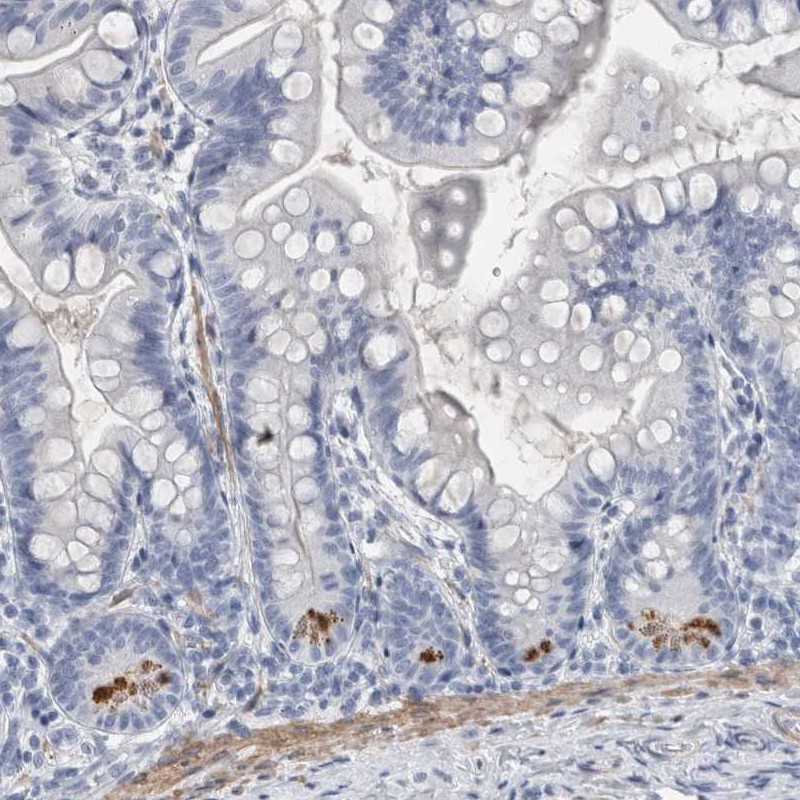

Immunohistochemical staining of human small intestine shows strong positivity in paneth cells.